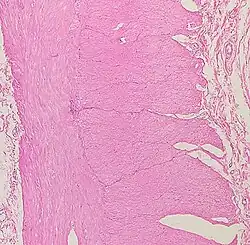

Histología del intestino grueso

Presenta criptas de Lieberkühn, no tiene vellosidades ni pliegues circulares.[44]

En el intestino grueso hay una gran cantidad de exocrinocitos caliciformes. Las poblaciones celulares epiteliales son las mismas del intestino delgado.[45][46]

La diferencia más obvia con el intestino delgado es que es más ancho y que presenta una capa muscular longitudinal que se reduce a tres estructuras en forma de correa, de unos 5 milímetros de anchura, conocidas como taeniae coli, que empiezan en la base del apéndice y se extienden desde el ciego hasta el recto.[2] La capa mucosa de su pared está formada por epitelio columnar simple y, en vez de tener las vellosidades del intestino delgado, el intestino grueso presenta criptas intestinales.[3] A pesar de que los dos intestinos tienen células en forma de cáliz, al intestino grueso son más numerosas. La serosa externa es otra capa de tejido conectivo muy delgada que se continúa focalmente con el peritoneo.